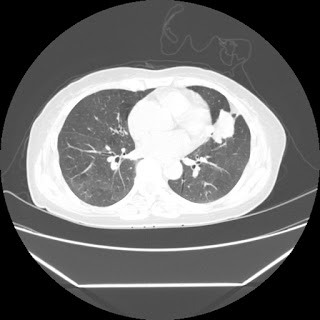

Radiological images:

HRCT is also done on 13/11/15